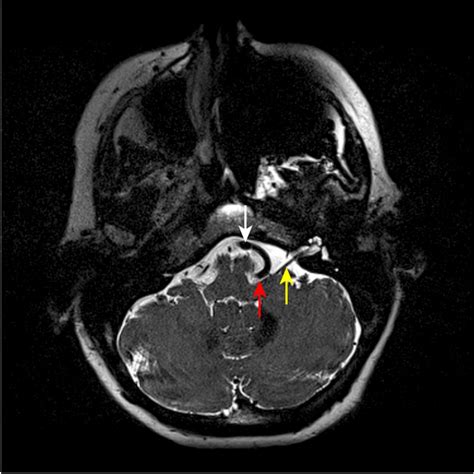

Hemifacial spasm is a neuromuscular disorder. It is important to distinguish it from other facial conditions, such as blepharospasm or facial tics. While tics are often psychological or related to habit, a hemifacial spasm is almost always caused by a physical abnormality: vascular compression of the facial nerve. This pressure causes the nerve to fire uncontrollably, leading to the characteristic muscle contractions.

For those seeking a definitive solution to stop the nerve compression, Microvascular Decompression (MVD) is considered the gold standard. Unlike injections, this is a surgical procedure performed by a neurosurgeon. The goal is to identify the blood vessel pressing against the facial nerve and insert a small sponge or "pad" between the vessel and the nerve to relieve the pressure.